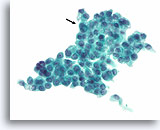

Afbeelding 24

Folliculair neoplasma, hurthleceltype, schildklier FNA, celblok.

Deze afbeelding van de patiënt in afbeelding 23 toont de uniformiteit van de hürthlecelpopulatie die, samen met het robuuste cytoplasma in microfollikels, pleit voor een hürthlecelneoplasma.

40X

Afbeelding 24

Folliculair neoplasma, hurthleceltype, schildklier FNA, celblok.

Deze afbeelding van de patiënt in afbeelding 23 toont de uniformiteit van de hürthlecelpopulatie die, samen met het robuuste cytoplasma in microfollikels, pleit voor een hürthlecelneoplasma.

40X